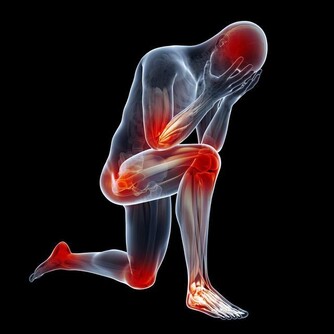

半夜小腿抽筋,發作時疼痛難忍,往往把人痛醒,有好長時間不能止痛,且影響睡眠。

腿抽筋原因有很多,最常見的是寒冷刺激,另外還有缺鈣、運動不當等。